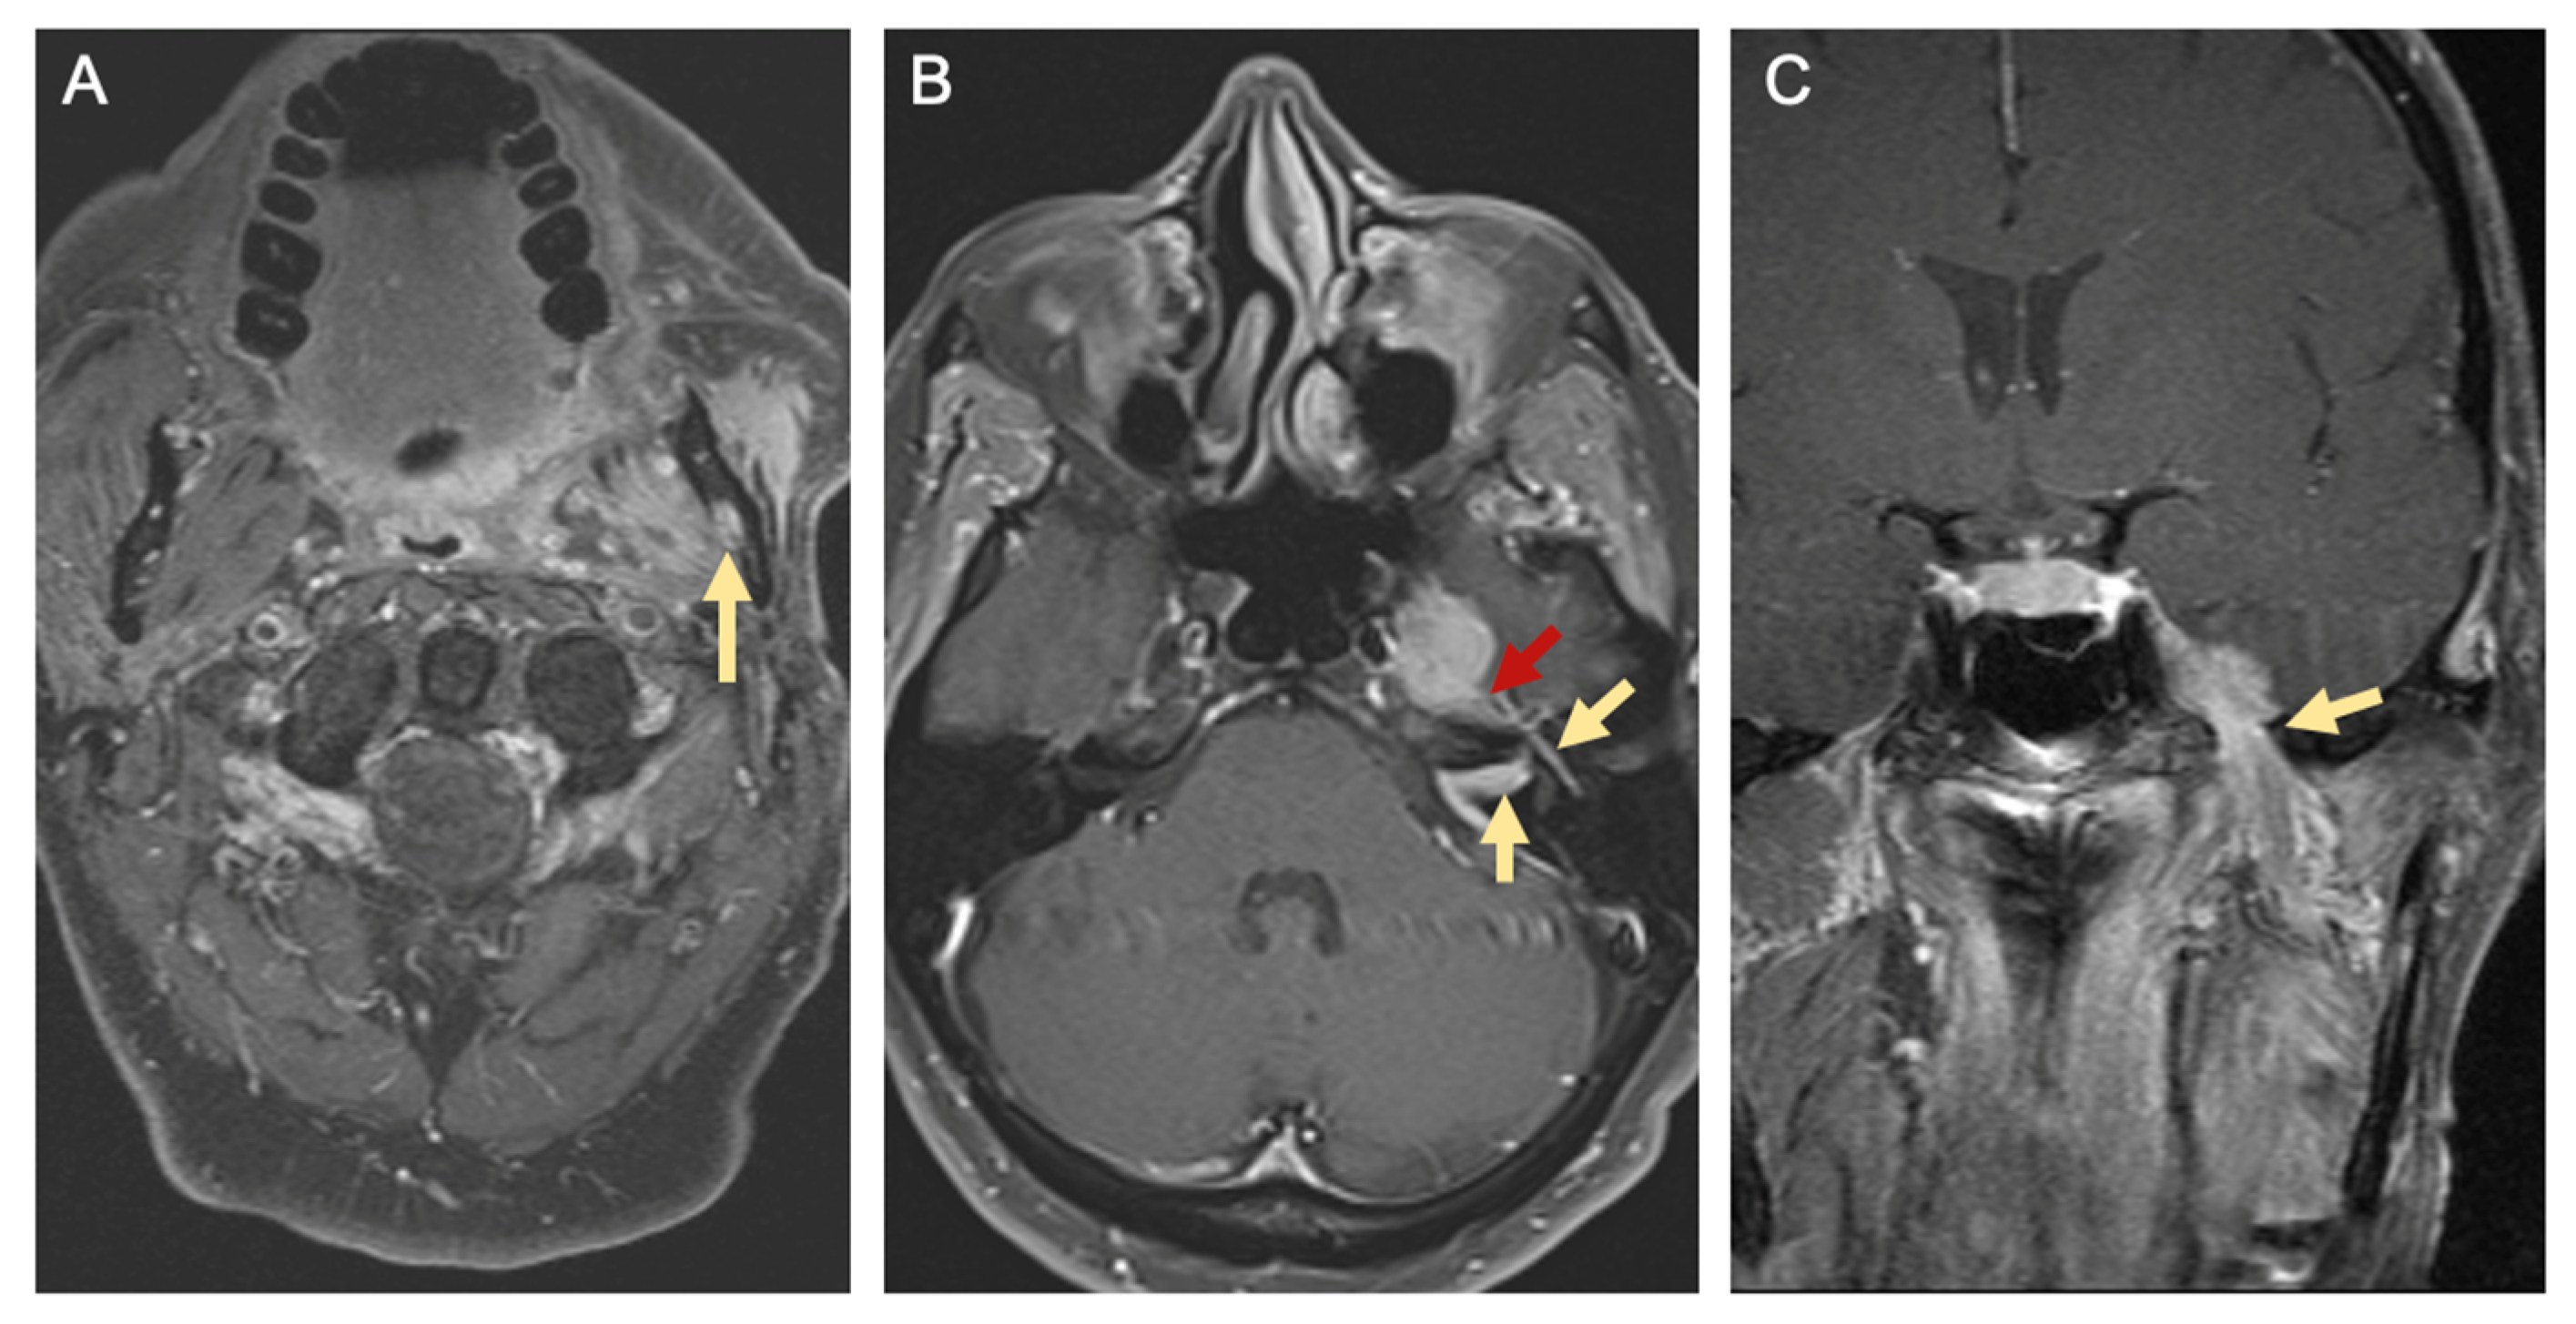

- Bakst, R.L.; Glastonbury, C.M.; Parvathaneni, U.; Katabi, N.; Hu, K.S.; Yom, S. Perineural Invasion and Perineural Tumor Spread in Head and Neck Cancer. Int. J. Radiat. Oncol. 2019, 103, 1109–1124. [Google Scholar] [CrossRef] [PubMed] [Green Version]

- Lee, H.; Lazor, J.W.; Assadsangabi, R.; Shah, J. An Imager’s Guide to Perineural Tumor Spread in Head and Neck Cancers: Radiologic Footprints on 18F-FDG PET, with CT and MRI Correlates. J. Nucl. Med. 2019, 60, 304–311. [Google Scholar] [CrossRef] [PubMed] [Green Version]

- Chong, V.-H. Imaging of perineural spread in head and neck tumours. Cancer Imaging 2010, 10, S92–S98. [Google Scholar] [CrossRef] [Green Version]